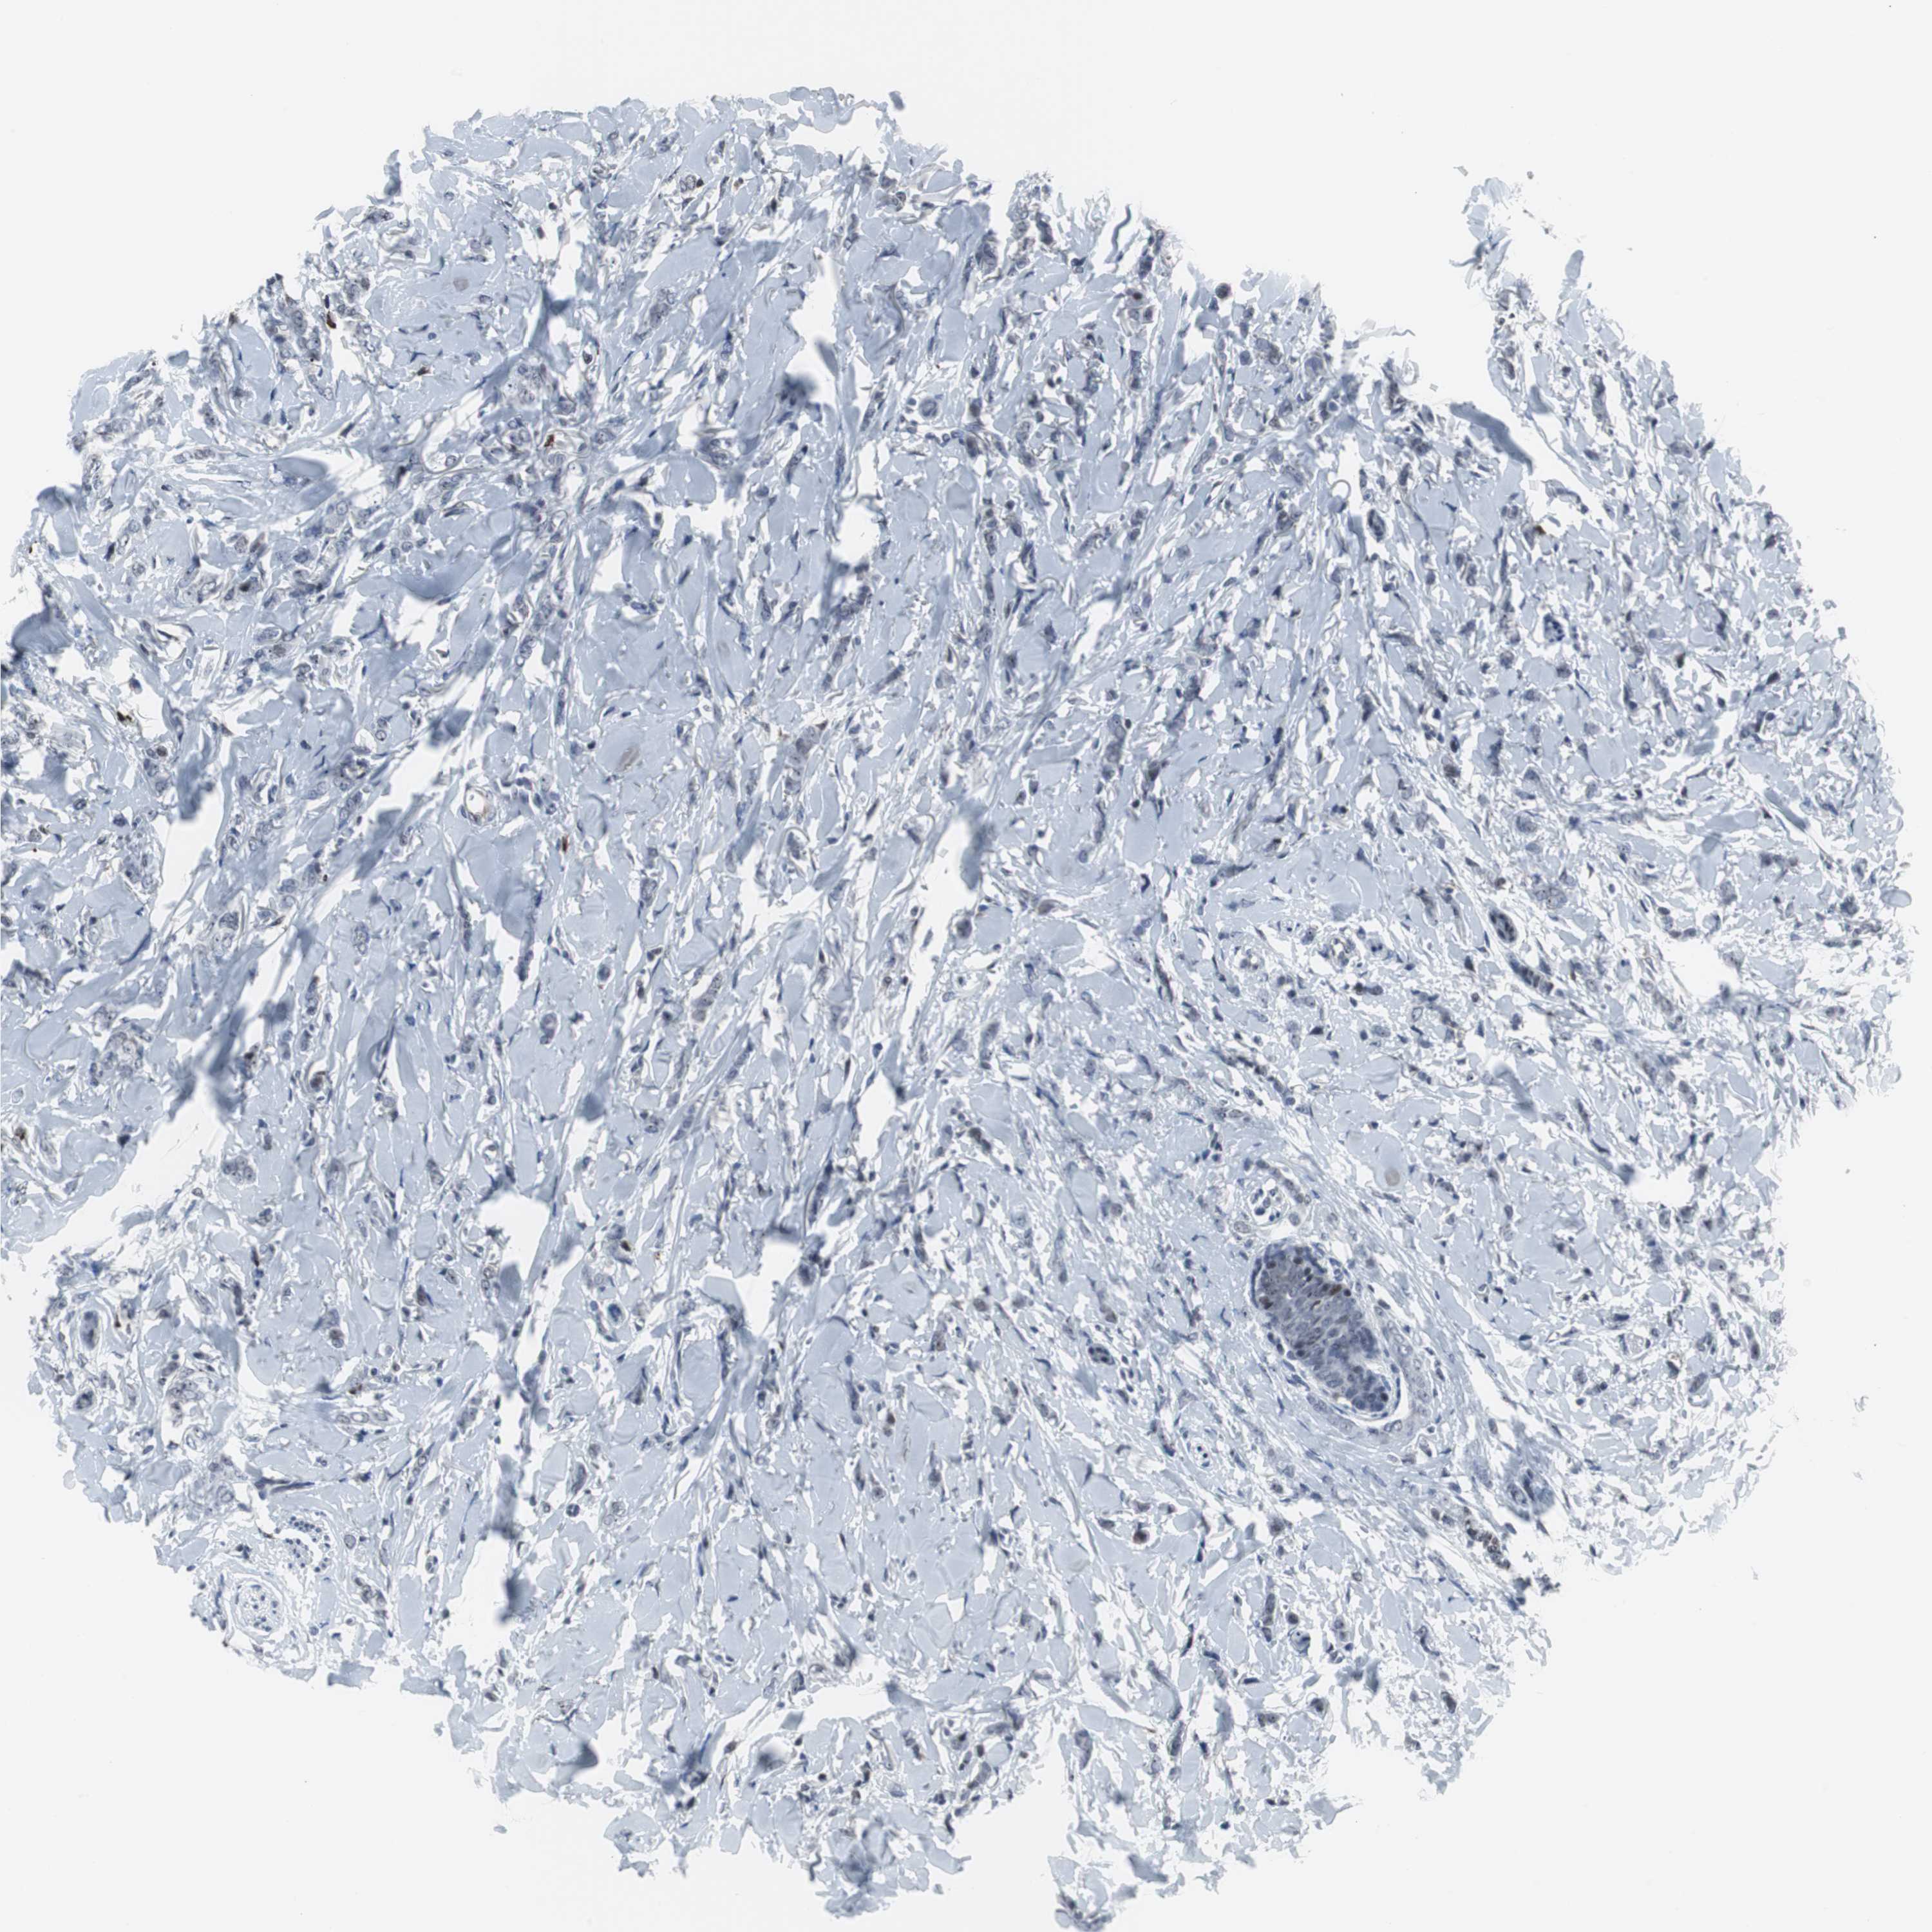

BRCA TCGA BRCA VALIDATION PROTEIN EXPRESSION